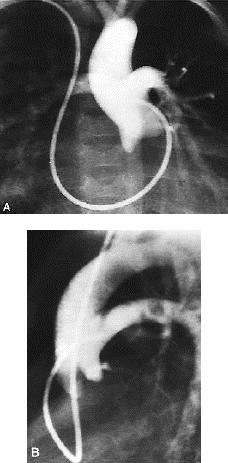

Sobre a patologia exibida nas seguintes imagens, é correto afirmar que

Provas